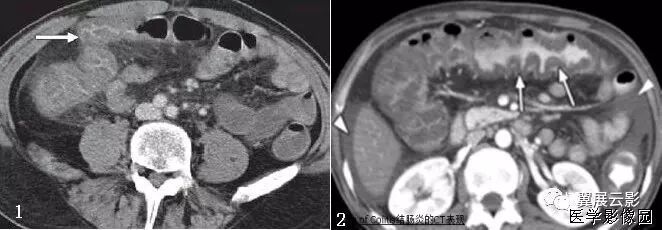

1、靶征(肠套叠)

是肠套叠最常见的特征性CT征像,为肠套叠长轴与CT扫描层面垂直时的表现,反映了套叠的各层肠壁、肠腔及肠系膜间的关系。典型排列为自外向内分别代表鞘部外层肠壁、鞘部肠腔内造影剂、鞘部内层肠壁、偏心性套入部肠系膜、套入部肠壁、套入部肠腔内造影剂。

肠套叠指:一段肠管及与其相连的肠系膜(套入部)被套如其相连的一段长管内(鞘部),导致肠内容物通过阻碍。婴儿由于大肠与小肠管径之比例相差大,故小肠易陷入大肠而被套牢。少数肠套叠可能来自某些器质性病变如美凯尔憩室、肠息肉、异位胰腺小结、血管瘤、异物、复制肠管、淋巴增生、肿瘤、寄生虫等,其中以美克尔憩室最多,过敏性紫斑也常会合并肠套叠,大于2岁的小孩发生肠套叠,一定要考虑到这些病变,大于5岁的病例中,则以淋巴瘤为最多;成人肠套叠小肠多见,常伴发良性病变;结肠型肠套叠则更多由恶性病变继发。良性病变有脂肪瘤、平滑肌瘤、血管瘤、神经纤维瘤、腺瘤样息肉、美克尔憩室、术后粘连以及动力性病变等;恶性病变有转移瘤、腺癌、类癌、淋巴瘤及平滑肌肉瘤等。由于肠套叠长轴与CT扫描层面的角度不同,表现各异。

如扫描层面和迂曲的肠道相平行时,表现为彗星尾征或肾形征:即套叠近端肠系膜血管牵拉聚拢的征象。一般情况下,慧星尾征均与肾型肿块相伴出现。该肾形肿块为套鞘部游离缘与套入部近端肠管及肠系膜的CT斜切面图像,其中游离的套鞘呈弧形围绕套入部,形状若肾轮廓外形,而套入部近端肠管、肠系膜形状若肾蒂。此时,所谓慧星尾征的组成还应包括套入近端肠管。如果套叠的肠管与CT扫描垂直,则呈靶形征,即肿块影表现为圆形或类似环形。通常在肿块内可分辨出层样结构,推测可能是继发于套入部和鞘部间的液体或是肠壁水肿造成密度对比,类似同心圆形;当套入部肠壁显著水肿坏死或套入部肿瘤周围浸润累及肠系膜,肠系膜血管及脂肪、套叠时间较长,套入部系膜血管受挤压时,静脉血液回流障碍,套入部肠壁充血水肿、变硬,形成不完全性肠梗阻,套叠以上肠管蠕动增强,可引起代偿性肠管扩张肥厚,并可见肠系膜连同其血管纠集、扭曲,形成“漩涡征”。